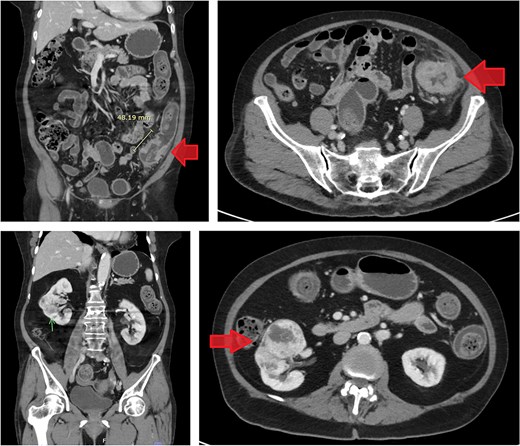

Computed tomography (CT) scan of the abdomen revealed a 5.2 mm polypoid lesion at the rectosigmoid colon without evidence of pericolonic fat extension, adjacent organ invasion, or regional/distant lymph node enlargement. Incidentally, a 5 cm hypervascular mass was noted at the lower pole of the right kidney, demonstrating peripheral enhancement with central low density. CT scan of the chest revealed no lymph node enlargement or pulmonary metastasis. On CT scan, the rectosigmoid colon mass exhibited radiologic characteristics suggestive of sigmoid colon cancer, while the lower pole right kidney mass demonstrated features consistent with RCC (Fig. 1).

Contrast-enhanced CT images of case 1. Top-left: Coronal view of the sigmoid colon cancer. Top-right: Transverse view of the CRC. Bottom-left: Coronal view of the renal cell carcinoma (RCC). Bottom-right: Transverse view of the RCC.